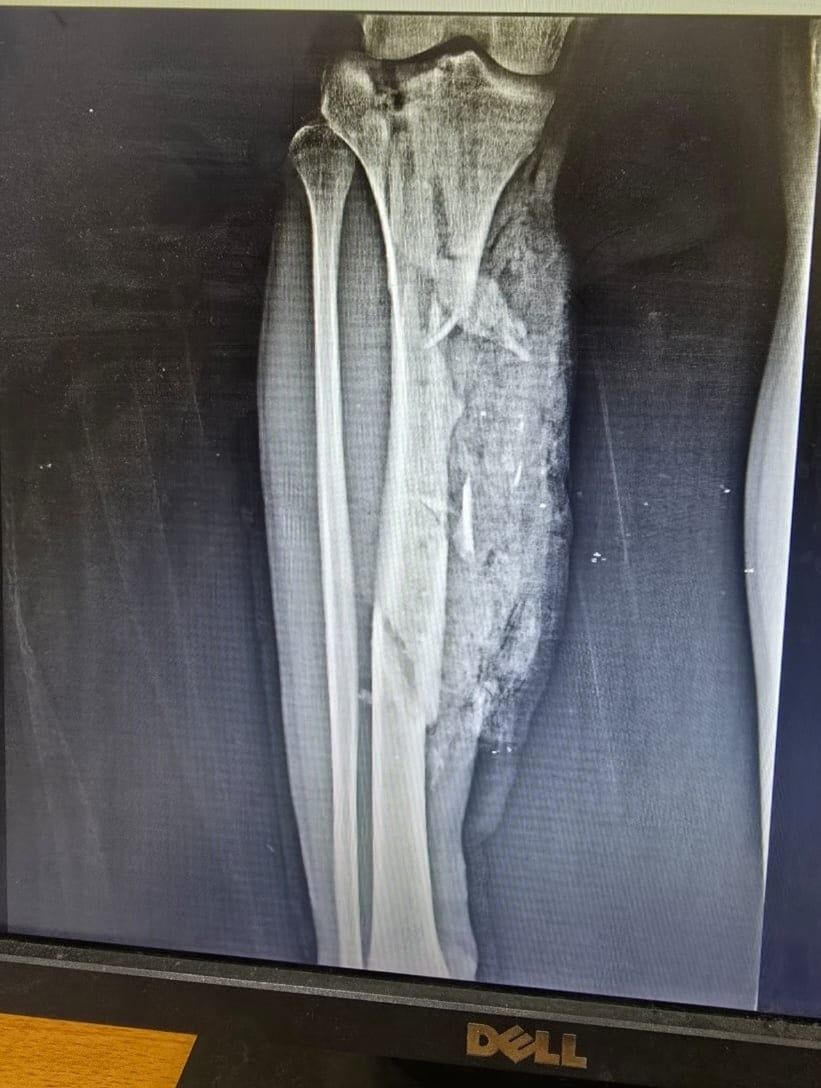

الإثنين، 06 أكتوبر 2025 01:50 منجح فريق جراحي بمستشفى قها التخصصي، التابعة لأمانة المستشفيات المتخصصة بوزارة الصحة، بمحافظة القليوبية، في إنقاذ حياة شاب في الـ20 من عمره، اصطدم به قطار، وكاد الحادث أن يودي بحياته، وتسبب في إصابته بكسر متفتت مفتوح مع فقد جزء من العظام بالعضد الأيمن مع قطع بالعضلات، وكسر متفتت مفتوح مع فقد جزء من العظام بالساق الأيمن مع قطع بالعضلات، وتهتك بالقدم اليمنى وقطع بالأوتار والعضلات، مع كسر بعظام القدم.

وتابعت المستشفى، أنه تم تجهيز المريض ولياقته من قسم التخدير وتحضيره وتجهيز الدم والبلازما اللازمة للحالة، حيث استقر التشخيص علي كسر متفتت مفتوح مع فقد جزء من العظام بالعضد الأيمن مع قطع بالعضلات، وكسر متفتت مفتوح مع فقد جزء من العظام بالساق الأيمن مع قطع بالعضلات، وتهتك بالقدم اليمنى وقطع بالأوتار والعضلات، مع كسر بعظام القدم.

كسور بجسم الشاب بعد الحادث

الأشعة الخاصة بالمريض